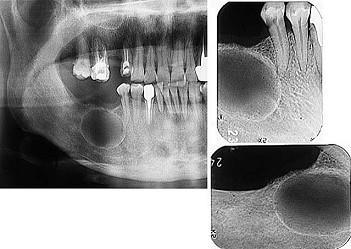

问题 发现下前牙变色,唇侧牙龈一肿物一月余,经X 线检查,结果如图。最可能的诊断是 ( )

选项 A.根尖囊肿 B.成釉细胞瘤 C.牙龈瘤 D.根尖脓肿 E.牙骨质瘤

答案 A